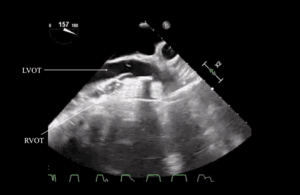

A bedside echocardiogram (VScan, GE) showed evidence of severe left ventricular and right ventricular thickening. Both atria were severely dilated. The mitral, tricuspid, and aortic valves appeared thickened. Myocardial speckling was not appreciated. Both the left and right ventricular function appeared to be moderately impaired.